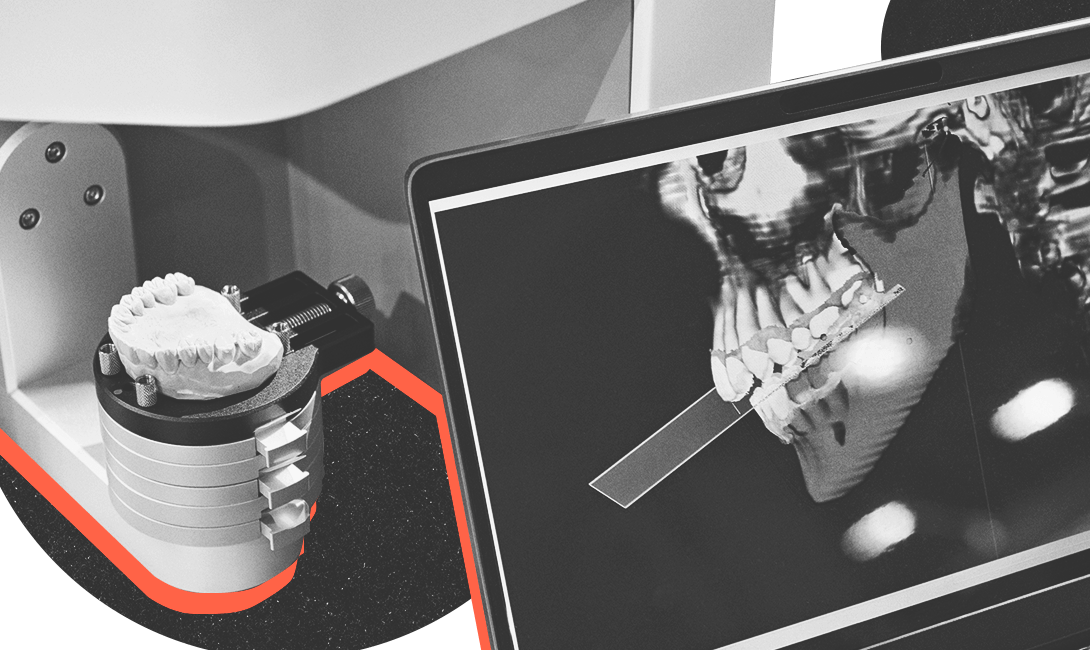

Не менее важно убедиться в том, что зуб-донор подходит по размеру к лунке зуба, который предстоит удалить. Для этого проводят предварительную примерку, распечатав трёхмерную модель зуба на 3D-принтере. Если форма и размер устраивают, можно начинать трансплантацию. Далее на рану накладываются швы, а пересаженный зуб осторожно фиксируется при помощи ортодонтической проволоки и резиновой тяги.

Помимо аутотрансплантации в PerfectSmile проводят все инновационные процедуры: от диагностики скрытого кариеса и лечения его под седацией до профессиональной гигиены полости рта на японском аппарате AirFlow и отбеливания зубов по системе Zoom4.

В каждом кабинете клиники есть стоматологический микроскоп для детального обследования. С его помощью удаётся увеличить место осмотра в 30 раз и выявить любую зубную болезнь ещё на стадии развития. Собственная зуботехническая лаборатория позволяет максимально быстро изготавливать различные индивидуальные конструкции – коронки, виниры, протезы и ортодонтические аппараты.